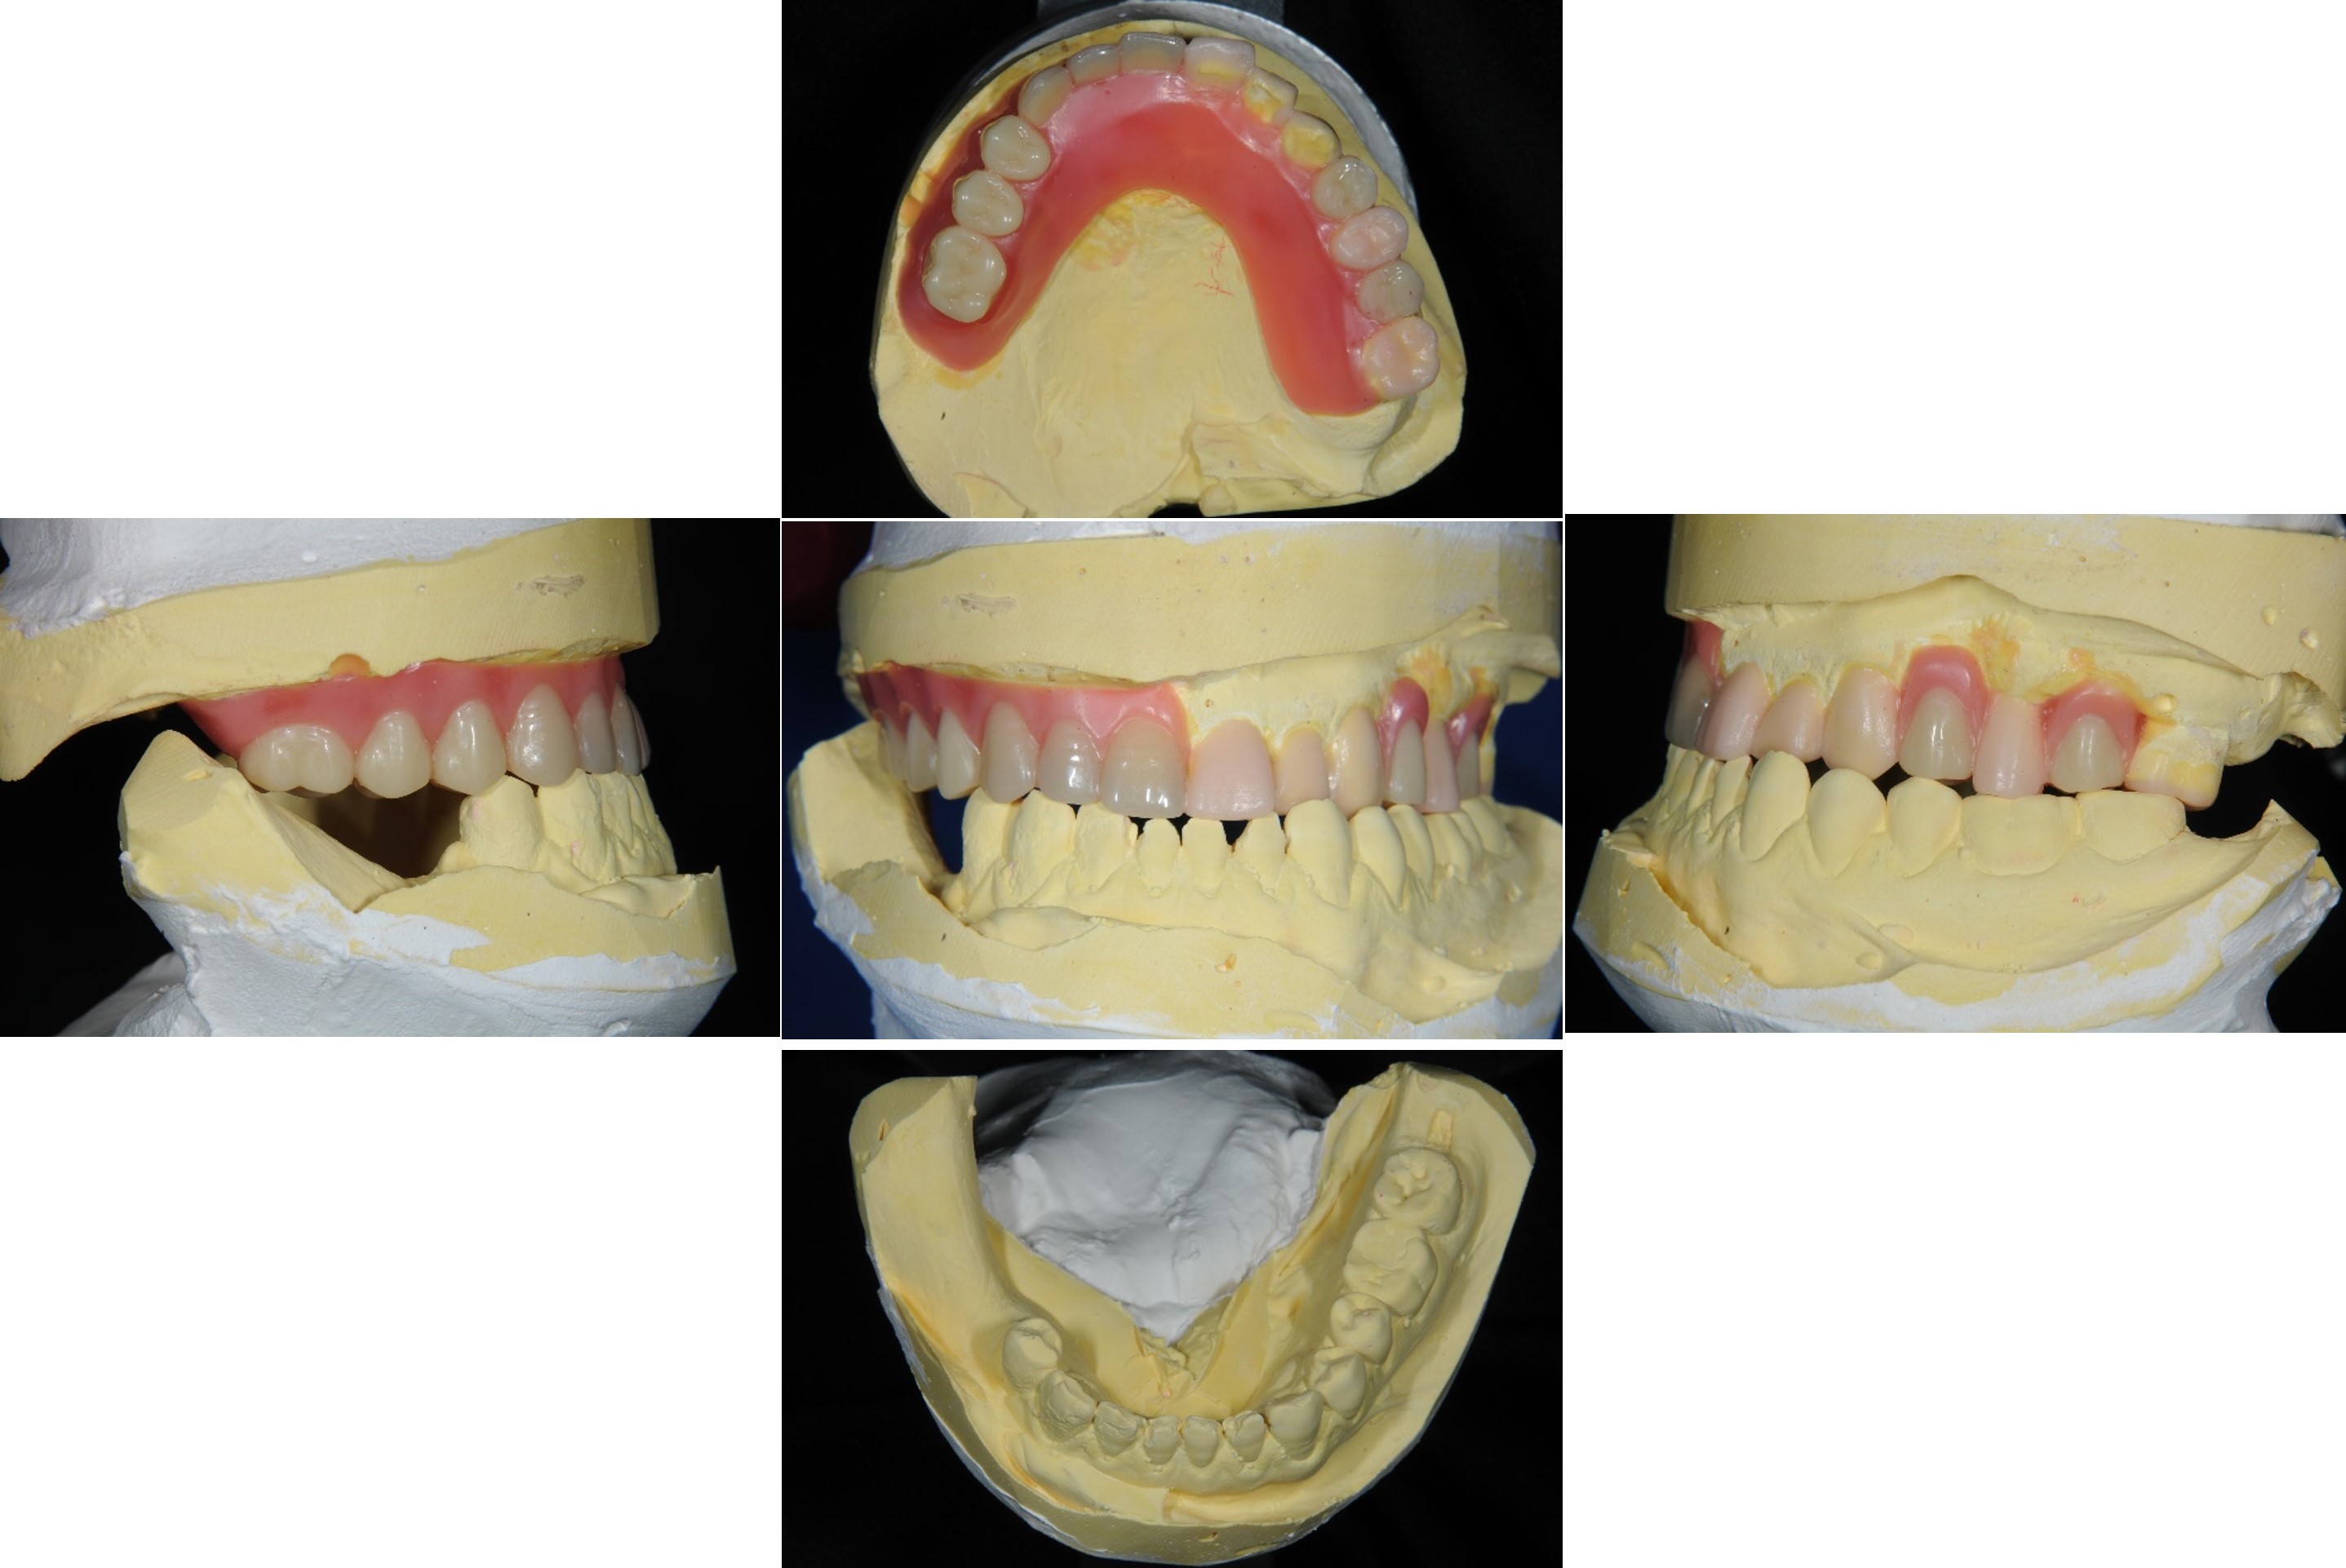

上下顎初步印模

模型咬合分析

蠟型模擬最終可能成果